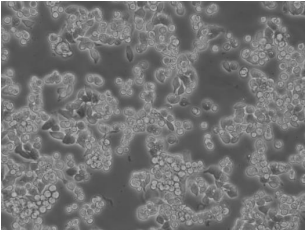

AMC-HN-8(人喉癌细胞),取自46岁男性供体淋巴转移组织,贴壁培养。

| 细胞形态 | 上皮细胞样 |

| 生长特性 | 贴壁细胞 |